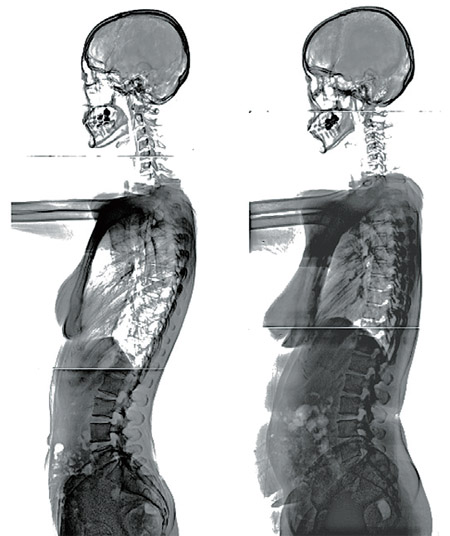

여기 37살 동년배의 동시대인 두 사람(사진)이 있다. 한쪽은 척추 곡선이 날렵하게 살아 있지만, 다른 한쪽은 배가 나오고 여기저기 살이 붙고 척추 곡선이 뻣뻣해지기 시작했다. 내가 오늘 어떤 음식을 얼마나 먹었는지, 얼마나 몸을 움직이고 운동을 했는지, 얼마나 즐겁고 감사한 마음으로 살았는지, 그런 하루하루가 모이고 쌓여서 그 결과가 나의 현재를 이루고 있다. 그리고 10년 뒤, 20년 뒤의 내 모습을 만들어갈 것이다. 알파벳 b와 d 사이에 무엇이 있는가? 무수한 c가 있다고 사르트르는 말했다. 탄생(birth)과 죽음(death) 사이에는 우리가 스스로 할 수 있는 무수한 선택(choice)이 있다. 어느 삶을 살겠는가? 전적으로 내 자신의 선택이다. 서울시립동부병원 정형외과 전문의